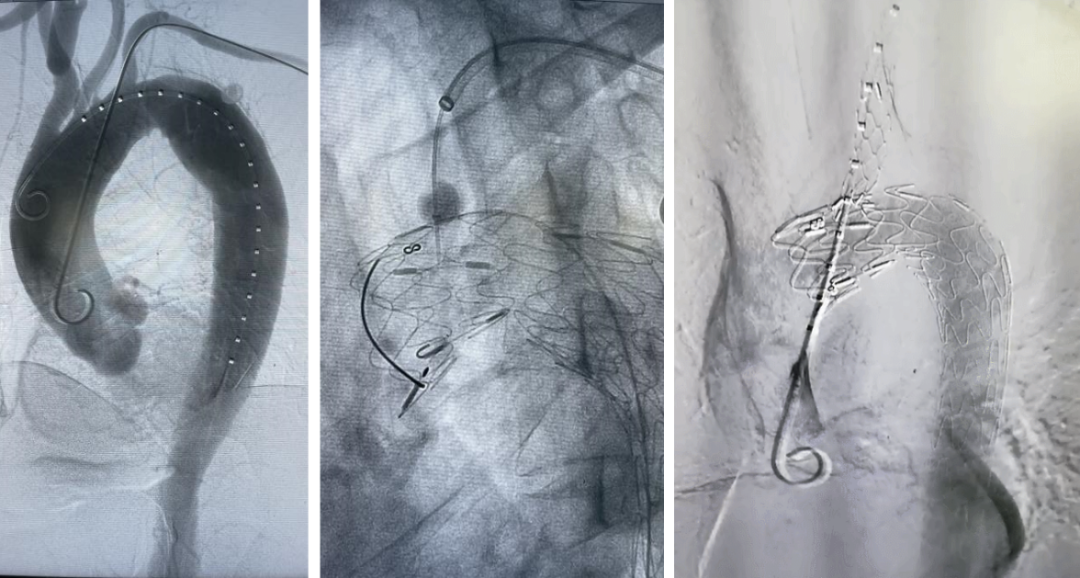

(术中主体支架成功锚定在迷走左椎开口后沿,原位破膜成功,并成功封堵大破口,主体、分支和迷走左椎均显影良好。)

(术后30天CTA显示,主体、分支、迷走动脉均通畅,弓上迷走动脉成功保留)